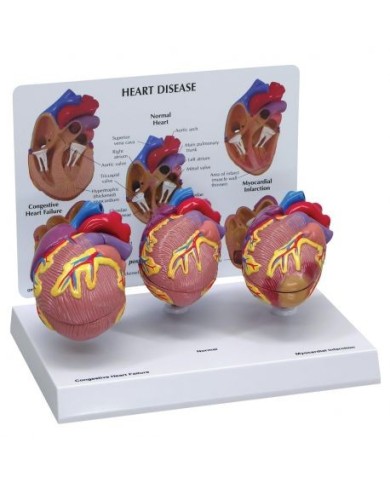

Kit composto da 3 modelli

Su Base, staccabile

Con scheda descrittiva dettagliata